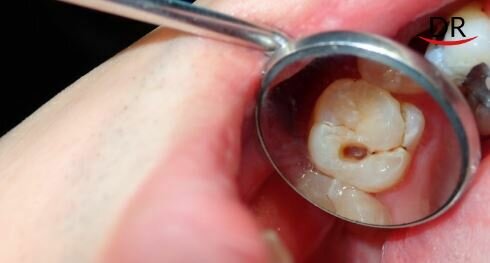

La radiografía dental es una técnica de imagenología que permite a los dentistas obtener imágenes detalladas de los dientes y los huesos de la mandíbula. Estas imágenes son esenciales para detectar problemas bucales como caries, tumores, posición de las piezas dentales, control previo y posterior a ortodoncia, y otros problemas estructurales.

Este estudio de imagen se ha convertido en una de las herramientas más efectivas para evaluar la salud dental de sus pacientes. Estas imágenes pueden revelar información que no puede ser perceptible a simple vista al examen físico general, como la presencia de caries ocupadas, problemas con las raíces y los huesos, y la presencia de abscesos o tumores, y mucho más allá.